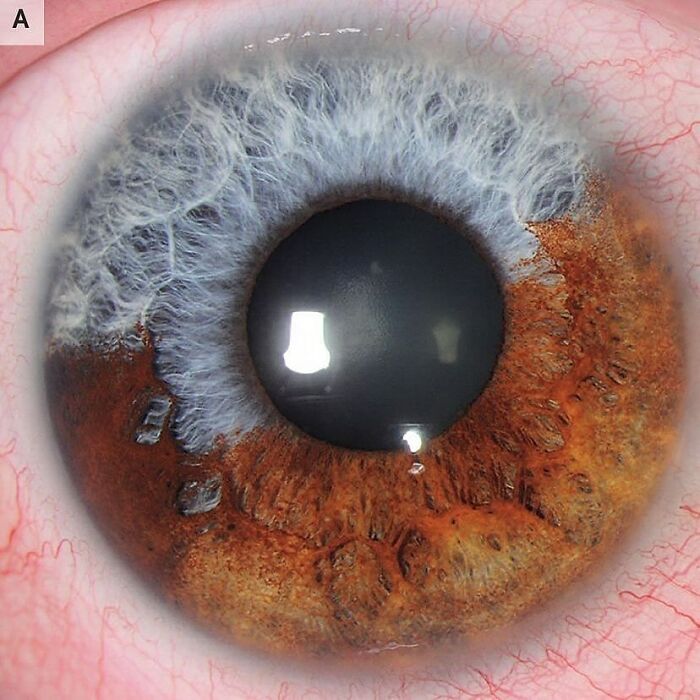

Conjunctival varices are abnormally dilated venous channels within the conjunctiva. They are typically freely mobile relative to the sclera. These venous malformations are usually asymptomatic and do not require any specific treatment. They can be excised for cosmetic reasons, but one should be aware that they may have orbital extensions